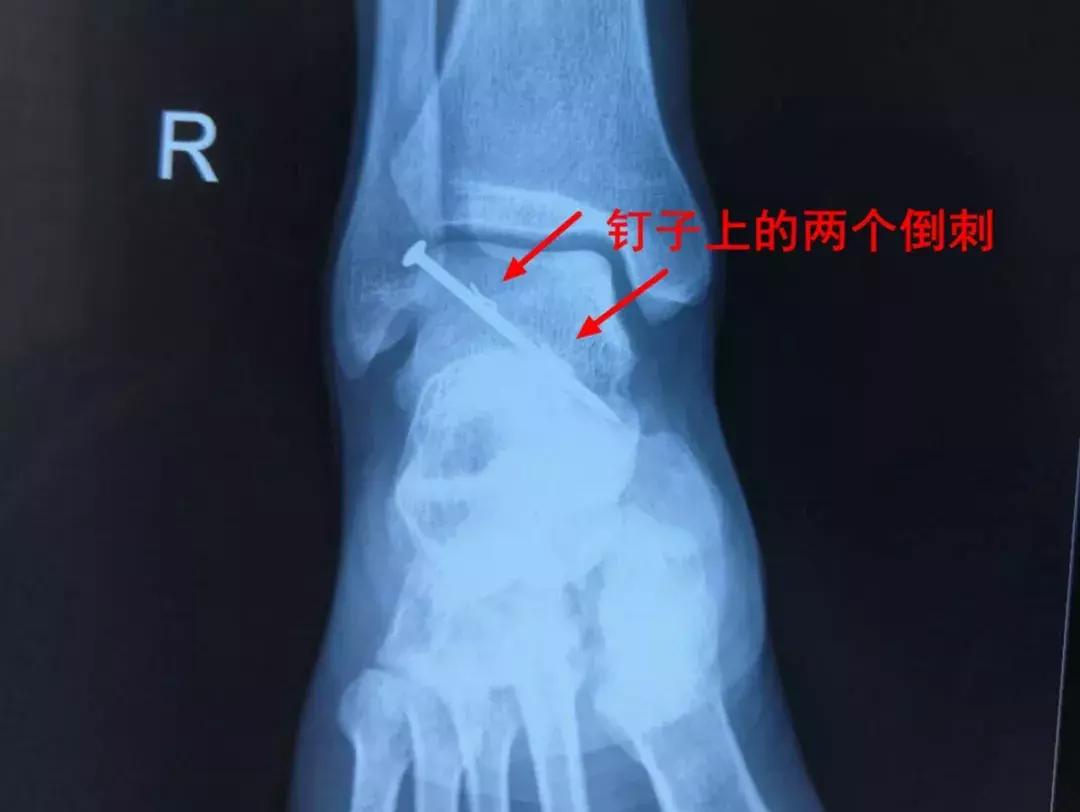

“当时只能看到一个钉帽露在外面,钢钉的具体长度及射入的位置无法确定。我们立即为他安排DR拍片检查。”栖霞市人民医院骨外二科刁新清主任说。拍片结果显示,这枚钢钉已经插入跟骨约三厘米,如处理不当可能导致跟骨断裂,造成肢体残疾,而且,这个钢钉还附着两根倒刺,进一步增加了手术难度。

“手术之前我们进行了仔细的评估、准备,决定为他实行微创手术。”刁新清主任说。手术在局部麻醉状态下进行,借助C型臂X光机引导,一点点拔出钢钉后,发现两根倒刺已经断在伤口里,医生又小心翼翼的将其取出,将骨骼受到的伤害降到最低,之后对伤口深处进行了清洗和消毒,以防感染。